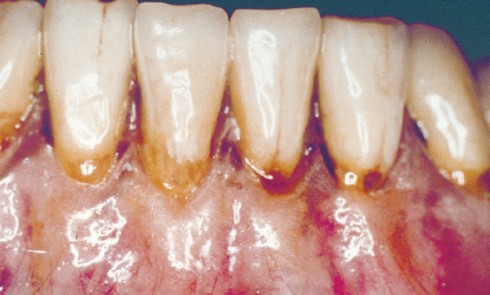

Article réservé à nos abonnés Dépister une maladie parodontale : comment être le plus efficace ?

Les maladies parodontales sont des maladies inflammatoires d’origine infectieuse et multifactorielle. Une étude épidémiologique publiée en 2007 (1) a montré...